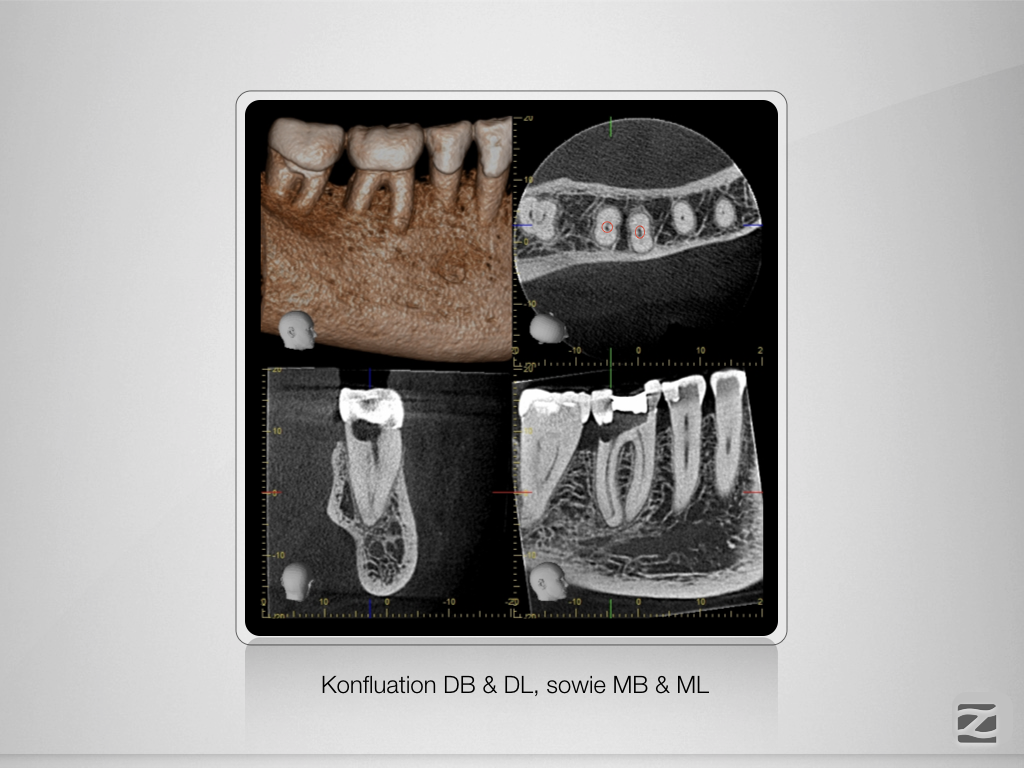

Tiefe Gabelung mit 90 Grad nach distal